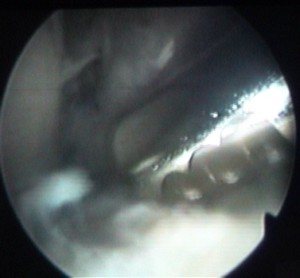

cette vis sert à attacher le ligament |

et elle est maintenant vissée à fond |